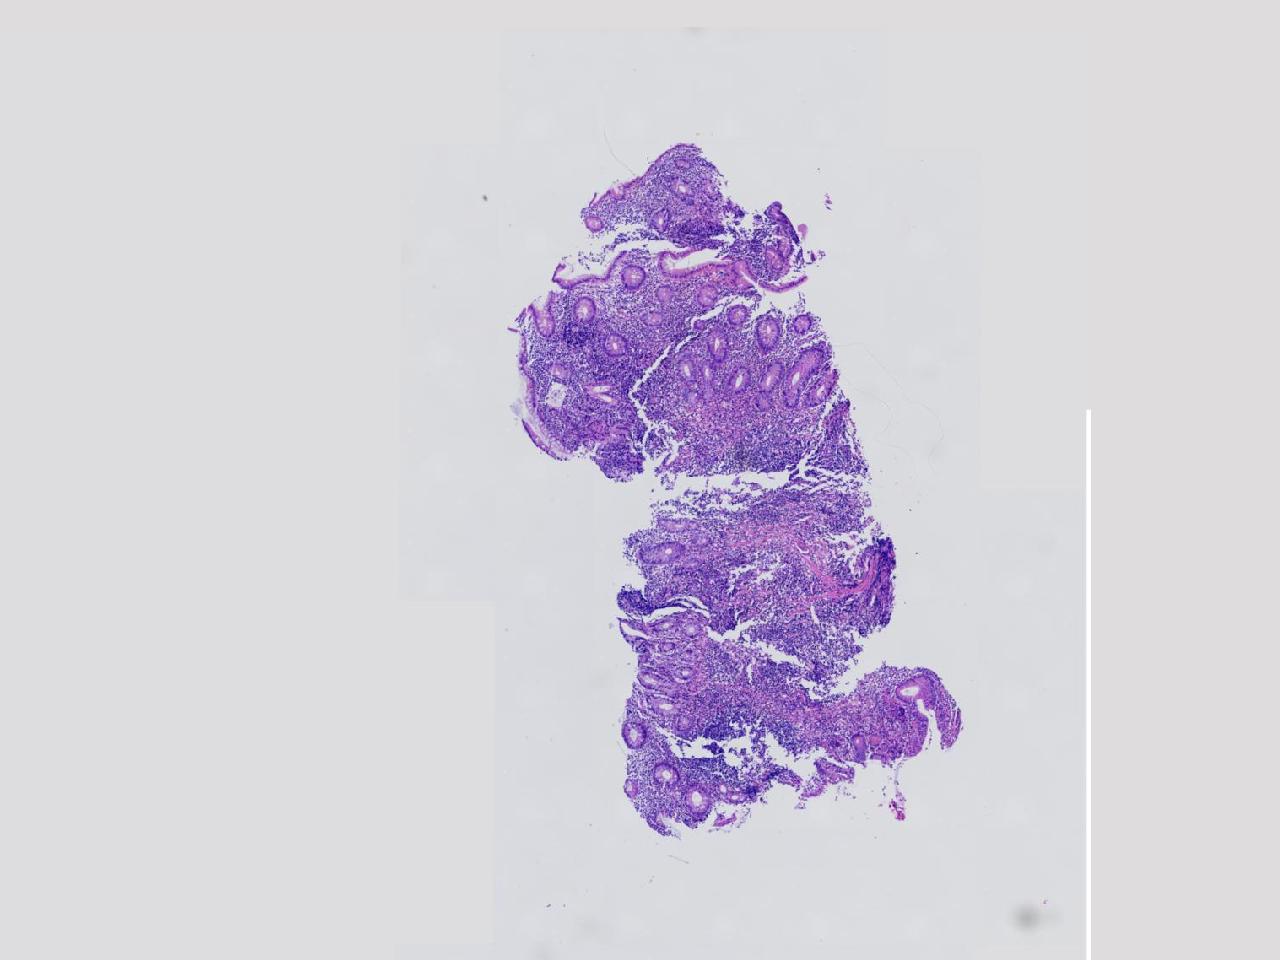

男,62岁,回盲部附近见多发片状溃疡,底覆薄白苔,周围粘膜充血水肿,活检2块,质软,弹性可。

回盲部活检

灰白色不整形软组织2块,直径均0.2厘米。

考虑:溃疡性结肠炎?

炎症性肠病要考虑,具体的类型不太好确定,需要结合临床。

上级医院会诊,不除外炎症性肠病,结合临床。